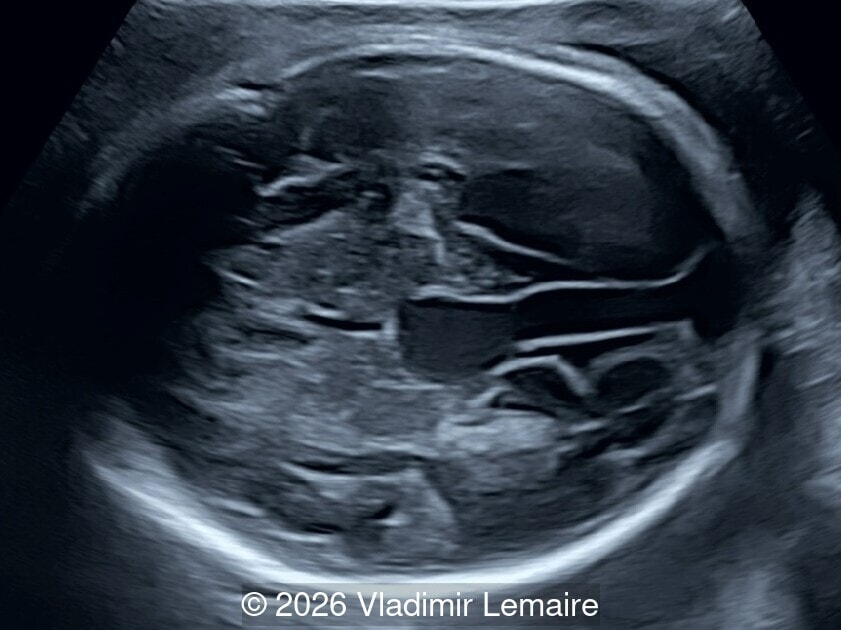

Transverse view of the upper abdomen at the level of the abdominal circumference.

Image 1 Transverse view of the upper abdomen at the level of the abdominal circumference.